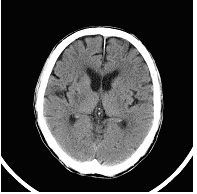

右側大腦阻塞性腦中風(電腦斷層(左)、核磁共振(右))